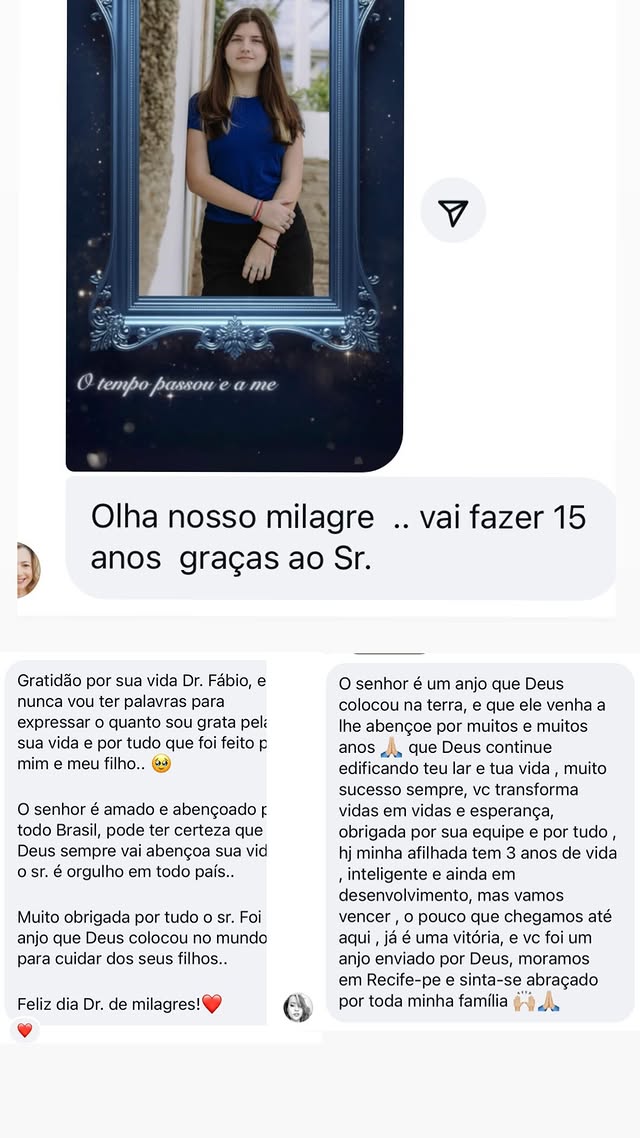

Esperança viva: descubra o futuro

que a Valentina conquistou

"Valentina é a prova de que a força nasce junto com a vida. Hoje inspira todos ao seu redor com sua coragem. Sua trajetória mostra que, com apoio, fé e amor, é possível transformar desafios em conquistas. Essa é a história de uma menina que não se limitou ao diagnóstico, mas abraçou o futuro com esperança viva."